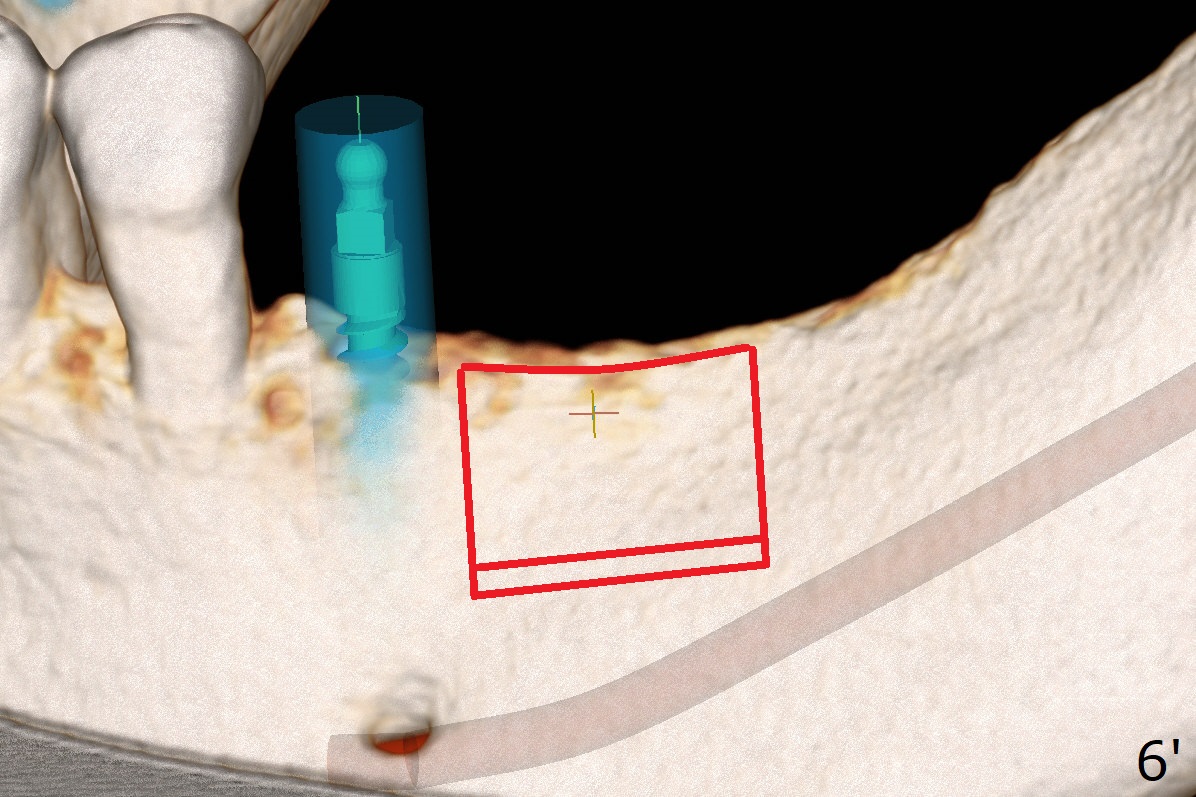

When implants at #4, 13 and 14 are placed, the patient wonders how many more implants are needed. From 0 (considering a lower RPD) to 5 (#3, 19, 20, 25 and 30). The tooth #3 seems to have periodontal-endodontic disease (Fig.1,2). Since the ridge is narrow at #19 and 20 (Fig.3), ridge split at #19 and a 1-piece implant at #20 are planned (Fig.4,5-9). The implant at #19 will be placed in an ideal prosthetic position (Fig.5). The ridge transverse bony cut will be made free hand in the middle (Fig.6,6'), followed by 2 vertical cuts and 1 apical transverse one in the 1st stage of procedure. In order to rotate the buccal block easier (Fig.6 pink curved arrow), the apical transverse cut will be wedge in shape (Fig.6 (red), 6' (double lines), 7 (black)). In the 2nd stage, the ridge top split will be extended by using a chisel (Fig.7 longer red line) and the buccal block will be pushed buccally (Fig.8). A guide will be seated to finish osteotomy (Fig.9 white) and implant placement.